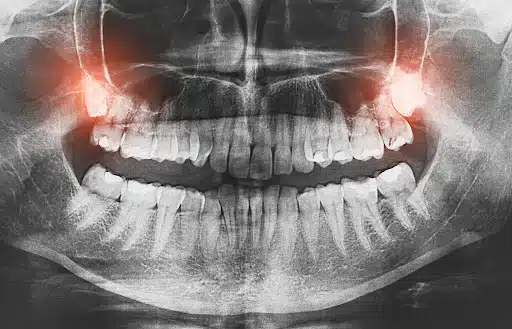

Wisdom teeth, also known as third molars, typically emerge between the ages of 17 and 25. Sometimes, they come in without problems. However, many people do not have enough space in their mouths, which can lead to complications.

Common issues include impacted teeth trapped under the gums, partial eruption where only part of the tooth emerges, infection or inflammation, and pressure on nearby teeth. These conditions can cause pain that may be constant or come and go over time.

Pain Before Removal (Impacted or Infected Teeth)

When wisdom teeth are impacted or infected, the pain tends to last longer and feel more intense. It can persist for days or weeks and may gradually worsen. Some people also experience pain that spreads to the jaw, ear, or head.